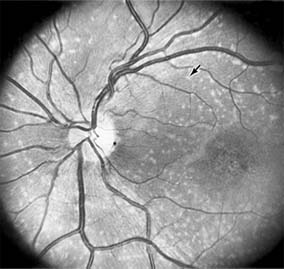

Chapter 10: Retina DISEASES OF THE MACULA AGE-RELATED MACULAR DEGENERATION Age-related macular degeneration is the leading cause of permanent blindness in the elderly. The exact cause is unknown, but the incidence increases with each decade over age 50. Other associations besides age include race (usually Caucasian), sex (slight female predominance), family history, and a history of cigarette smoking. The disease includes a broad spectrum of clinical and pathologic findings that can be classified into two groups: nonexudative ("dry") and exudative ("wet"). Although both types are progressive and usually bilateral, they differ in their manifestations, prognosis, and management. The more severe exudative form accounts for approximately 90% of all cases of legal blindness due to age-related macular degeneration. 1. NONEXUDATIVE MACULAR DEGENERATION Nonexudative age-related macular degeneration is characterized by variable degrees of atrophy and degeneration of the outer retina, retinal pigment epithelium, Bruch's membrane and choriocapillaris. Of the ophthalmoscopically visible changes in the retinal pigment epithelium and Bruch's membrane, drusen are the most typical (Figure 10-1). Drusen are discrete, round, yellow-white deposits of variable size beneath the pigment epithelium and are scattered throughout the macula and posterior pole. With time, they may enlarge, coalesce, calcify, and increase in number. Histopathologically, most drusen consist of focal collections of eosinophilic material lying between the pigment epithelium and Bruch's membrane; they therefore represent focal detachment of the pigment epithelium. In addition to drusen, clumps of pigment irregularly dispersed within depigmented areas of atrophy may progressively appear throughout the macula. The level of associated visual impairment is variable and may be minimal. Fluorescein angiography demonstrates irregular patterns of retinal pigment epithelial hyperplasia and atrophy. Electrophysiologic testing in most patients is normal. There is no generally accepted treatment or means of prevention of this type of macular degeneration. Laser retinal photocoagulation appears to have a beneficial effect on drusen but has not yet been shown to improve visual outcome. Although high plasma levels of antioxidants are associated with a reduced risk of age-related macular degeneration, the use of vitamin supplements does not appear to be preventive. Most patients with macular drusen never experience significant loss of central vision; the atrophic changes may stabilize or progress slowly. However, the exudative stage may develop suddenly at any time, and in addition to regular ophthalmic examinations, patients are given an Amsler grid ( 2. EXUDATIVE MACULAR DEGENERATION Although patients with age-related macular degeneration usually manifest nonexudative changes only, the majority of patients who experience severe vision loss from this disease do so from the development of subretinal neovascularization and related exudative maculopathy. Serous fluid from the underlying choroid can leak through small defects in Bruch's membrane, causing focal detachment of the pigment epithelium. Additional fluid may lead to further separation of the overlying sensory retina, and vision usually decreases if the fovea is involved. Retinal pigment epithelial detachments may spontaneously flatten, with variable visual results, and leave a geographic area of depigmentation at the involved site. Ingrowth of new vessels from the choroid into the subretinal space is the most important change that predisposes patients with drusen to macular detachment and irreversible loss of central vision. These new vessels grow in a flat cartwheel or sea-fan configuration away from their site of entry into the subretinal space. The clinical changes of early subretinal neovascularization are subtle and may be easily overlooked; during this occult stage of new vessel formation, the patient is asymptomatic, and the new vessels may not be apparent either ophthalmoscopically or angiographically. The ophthalmologist must maintain a high index of suspicion that subretinal neovascularization is present whenever a patient with evidence of age-related macular degeneration has sudden or recent central vision loss, including blurred vision, distortion, or a new scotoma. If the fundus examination reveals subretinal blood, exudate, or a grayish-green choroidal lesion in the macula, there is great likelihood that neovascularization is present, and a fluorescein or indocyanine green angiogram should be obtained promptly to determine if a treatable lesion can be identified. Although some subretinal neovascular membranes may spontaneously regress, the natural course of subretinal neovascularization in age-related macular degeneration is toward irreversible loss of central vision over a variable period of time. The sensory retina may be damaged by long-standing edema, detachment, or underlying hemorrhage. Furthermore, a hemorrhagic detachment of the retina may undergo fibrous metaplasia, resulting in an elevated subretinal mass called a disciform scar. This elevated fibrovascular mound of variable size represents the cicatricial end stage of exudative age-related macular degeneration. It is usually centrally located and results in permanent loss of central vision. Treatment In the absence of subretinal neovascularization, no medical or surgical treatment of serous retinal pigment epithelial detachment is of proved benefit. The use of parenteral alpha interferon, for example, has not been effective for this disease. However, if a well-defined extrafoveal ( Krypton laser photocoagulation of juxtafoveal (<200 Following successful photocoagulation of a subretinal neovascular membrane, recurrent neovascularization either contiguous with or remote from the laser scar may occur in one-half of cases by 2 years. Recurrence is often accompanied by severe vision loss, so that careful monitoring with Amsler grids, ophthalmoscopy, and angiography is essential. Low-dose radiotherapy has provided encouraging results in patients with subfoveal neovascularization. Patients with impaired central vision in both eyes may benefit from a variety of low vision aids. CENTRAL SEROUS CHORIORETINOPATHY Central serous chorioretinopathy is characterized by serous detachment of the sensory retina as a consequence of focal leakage of fluid from the choriocapillaris through a defect in the retinal pigment epithelium (Figures 10-2 and 10-3). This disease typically affects young to middle-aged men and may be related to life stress events. Most patients present with the sudden onset of blurred vision, micropsia, metamorphopsia, and central scotoma. Visual acuity is often only moderately decreased and may be improved to near-normal with a small hyperopic correction. The diagnosis is made by slitlamp examination of the fundus; the presence of serous detachment of the sensory retina in the absence of ocular inflammation, subretinal neovascularization, an optic pit, or a choroidal tumor is diagnostic. The retinal pigment epithelial lesion appears as a small, round or oval, yellowish-gray spot that is variable in size and may be difficult to detect without the aid of fluorescein angiography. Fluorescein dye leaking from the choriocapillaris may accumulate below the pigment epithelium or sensory retina, resulting in a variety of patterns including the well-recognized smokestack configuration. Approximately 80% of eyes with central serous chorioretinopathy undergo spontaneous resorption of subretinal fluid and recovery of normal visual acuity within 6 months after the onset of symptoms. Despite normal acuity, however, many patients have a mild permanent visual defect, such as a decrease in color sensitivity, micropsia, or relative scotoma. Twenty to 30 percent of patients will have one or more recurrences of the disease, and complications-including subretinal neovascularization and chronic cystoid macular edema-have been described in patients with frequent and prolonged serous detachments. The cause of central serous chorioretinopathy is unknown; there is no convincing evidence that the disease is either infectious or due to retinal pigment epithelial dystrophy. Argon laser photocoagulation directed to the active leak significantly shortens the duration of the sensory detachment and hastens the recovery of central vision, but there is no evidence that prompt photocoagulation reduces the chance of permanent loss of visual function. Although the complications of retinal laser photocoagulation are few, it is probably not advisable to recommend immediate photocoagulation treatment in all patients with central serous chorioretinopathy. The duration and location of disease, the condition of the fellow eye, and occupational visual requirements are all considerations upon which treatment decisions are based. MACULAR EDEMA Retinal edema involving the macula may be associated with a variety of intraocular inflammatory diseases, retinal vascular diseases, intraocular surgery, inherited or acquired retinal degenerations, medications, macular membranes, or unknown causes. Macular edema may be diffuse, with nonlocalized intraretinal fluid causing thickening of the macula. When edema fluid accumulates in honeycomb-like spaces of the outer plexiform and inner nuclear layers, it is called cystoid macular edema. On fluorescein angiography, fluorescein dye leaks from the perifoveal retinal capillaries and accumulates in a flower-petal pattern about the fovea (Figure 10-4). The most widely recognized association with cystoid macular edema is intraocular surgery. Approximately 50% of eyes undergoing uneventful intracapsular cataract extraction and 20% of eyes undergoing extracapsular cataract extraction develop angiographic cystoid macular edema. Clinically significant edema usually occurs within 4-12 weeks postoperatively, but in some instances its onset may be delayed for months or years. Many patients with cystoid macular edema of less than 6 months' duration have self-limited leakage that will resolve without treatment. Topical or local (or both) anti-inflammatory therapy may be of value in restoring visual acuity in some patients with chronic postoperative macular edema. YAG laser vitreolysis (see Chapter 24) and surgical vitrectomy may be of benefit when the macular edema is associated with vitreous tissue incarcerated in the cataract wound or adherent to anterior segment structures. When an intraocular lens implant is the cause of postoperative macular edema due to its design, positioning, or inadequate fixation, removal of the lens implant can be considered. INFLAMMATORY DISORDERS INVOLVING THE MACULA Presumed Ocular Histoplasmosis Syndrome (Figures 10-5, 10-6 and 10-7) In this disease, serous and hemorrhagic detachments of the macula are associated with multiple peripheral atrophic chorioretinal scars and peripapillary chorioretinal scarring (see Chapter 7). The syndrome usually occurs in healthy patients between the third and sixth decades of life, and the scars are probably caused by an antecedent subclinical systemic infection with Histoplasma capsulatum. The macular detachments are due to subretinal neovascularization, and the visual prognosis depends on the proximity of the neovascular membrane to the center of the fovea. If the membrane extends inside the foveal avascular zone, only 15% of eyes will retain 20/40 vision. A macular scar may change over time, and 10% of patients with normal maculae will develop new atrophic scars in this region. The relative risk of developing macular subretinal neovascularization in the second eye of an affected patient is significant, and these patients should be instructed in the frequent use of the Amsler grid and the importance of prompt examination when changes are detected. Argon laser photocoagulation of a subretinal neovascular membrane outside the foveal avascular zone in symptomatic patients is of value in preventing severe vision loss. The surgical removal of submacular membranes may prove useful in preserving vision. Acute Multifocal Posterior Placoid Pigment Epitheliopathy (AMPPPE) AMPPPE typically affects healthy young patients who develop rapidly progressive bilateral vision loss in association with ophthalmoscopically visible multifocal flat gray-white subretinal lesions involving the pigment epithelium (Figure 10-8). The cause of this disease, which in many instances is associated with evidence of an influenza-like illness, is unknown; the course and nature of the illness suggests the possibility of viral infection. The characteristic feature of the disease is the rapid resolution of the fundus lesions and a delayed return of visual acuity to near-normal levels. Although the prognosis for visual recovery in this acute self-limited disease is good, many patients will identify small residual paracentral scotomas when carefully tested. Extensive pigmentary changes remaining during the late stages of AMPPPE may mimic widespread retinal degeneration; the clinical history and normal electrophysiologic findings aid in this differential diagnosis. Geographic Helicoid Peripapillary Choroidopathy This is a chronic progressive and recurrent multifocal inflammatory disease of the retinal pigment epithelium, choriocapillaris, and choroid. It characteristically involves the juxtapapillary retina and extends radially to involve the macula and peripheral retina. The active stage manifests itself as sharply demarcated gray-yellow lesions with irregular borders that appear to involve the pigment epithelium and choriocapillaris. Vitritis, anterior uveitis, and subretinal neovascularization have been associated with this disorder. Involvement is usually bilateral, and the cause is unknown. The natural history of this indolent inflammatory disease is variable and may correlate with the presence of disease in the fellow eye. Local or systemic corticosteroid treatment may be of benefit when active inflammation is present; laser photocoagulation is administered as indicated for the complication of subretinal neovascularization. Vitiliginous Chorioretinitis (Birdshot Retinochoroidopathy) This is a syndrome characterized by diffuse cream-colored patches at the level of the pigment epithelium and choroid, retinal vasculitis associated with cystoid macular edema, and vitritis. The associations with HLA-A29 and with retinal S-antigen suggest that this disease has a genetic predisposition and that retinal autoimmunity plays a role in its manifestations. In many cases, electroretinography, electro-oculography, and dark adaptation studies are abnormal. The course of the disease is that of exacerbation and remission with variable visual outcomes; visual loss has been attributed to chronic cystoid macular edema, optic atrophy, macular scarring, or subretinal neovascularization. Corticosteroid therapy has not proved effective against this disease. Acute Macular Neuroretinopathy Acute macular neuroretinopathy is characterized by the acute onset of paracentral scotomas and mild visual acuity loss accompanied by wedge-shaped parafoveal retinal lesions in the deep sensory retina of one or both eyes. The macular lesions are subtle, reddish-brown, and best seen with a red-free light. The patients are usually young adults with a history of acute viral illness. While the retinal lesions may fade, the scotomas tend to persist and remain symptomatic. Multiple Evanescent White Dot Syndrome This is an acute and self-limited unilateral disease that affects mainly young women and is characterized clinically by multiple white dots at the level of the pigment epithelium, vitreal cells, and transient electroretinographic abnormalities. The cause is unknown. There is no evidence of associated systemic disease. The retinal lesions gradually regress in a matter of weeks, leaving only minor retinal pigment epithelial defects. ANGIOID STREAKS Angioid streaks appear as irregular, jagged tapering lines that radiate from the peripapillary retina into the macula and peripheral fundus (Figure 10-9). The streaks represent linear crack-like dehiscences in Bruch's membrane. The lesions are rarely noted in children and probably develop in the second or third decade of life. Early in the disease the streaks are sharply outlined and red-orange or brown. Subsequent fibrovascular tissue growth may partially or totally obscure the streak margins. Nearly 50% of patients with angioid streaks have an associated systemic disease. Pseudoxanthoma elasticum, Paget's disease of bone, Ehlers-Danlos syndrome, and several hemoglobinopathies and hemolytic disorders have been associated with this retinal disease, but the most common association is with age-related degeneration of Bruch's membrane. Patients with angioid streaks should be warned of the potential risk of choroidal rupture from even relatively mild eye trauma. Older patients with the disease are at risk of developing serous and hemorrhagic detachments of the retina as a consequence of subretinal neovascularization. Laser treatment may be used to photocoagulate extrafoveal neovascular membranes; however, other neovascular membranes are likely to occur. Prophylactic treatment of angioid streaks before subretinal neovascularization develops is not recommended. MYOPIC MACULAR DEGENERATION Pathologic myopia is one of the leading causes of blindness in the United States and is characterized by progressive elongation of the eye with subsequent thinning and atrophy of the choroid and pigment epithelium in the macula. Peripapillary chorioretinal atrophy and linear breaks in Bruch's membrane ("lacquer cracks") are characteristic findings on ophthalmoscopy (Figure 10-10). The degenerative changes of the macular pigment epithelium resemble those found in the older patient with age-related macular degeneration. A characteristic lesion of this disease is a raised, circular, pigmented macular lesion called a Fuchs spot. Most patients are in the fifth decade when the degenerative macular changes cause a slowly progressive loss of vision; rapid loss of visual acuity is usually caused by serous and hemorrhagic macular degeneration overlying a subretinal neovascular membrane. Fluorescein angiography in patients with pathologic myopia may show delayed filling of choroidal and retinal blood vessels. Angiography is helpful in identifying and locating the site of subretinal neovascularization in patients who develop serous or hemorrhagic detachments of the macula. Because of the frequent close proximity of the subretinal neovascular membrane to the foveola in these patients, laser photocoagulation may not be possible. As subretinal neovascular membranes tend to remain small and because photocoagulation-associated chorioretinal atrophy tends to progress in patients with pathologic myopia, retinal laser treatment is not as beneficial as in other diseases associated with macular subretinal neovascularization. The chorioretinal changes of pathologic myopia predispose the retina to breaks and thus to retinal detachment. Peripheral retinal findings may include paving stone degeneration, pigmentary degeneration, and lattice degeneration. Retinal breaks usually occur in areas involved with chorioretinal lesions, but they also arise in areas of apparently normal retina. Some of these breaks, particularly those of the "horseshoe" and round retinal tear type, will progress to rhegmatogenous retinal detachment. MACULAR HOLE A macular hole is a partial or full-thickness absence of the sensory retina in the macula. This disorder occurs most often in elderly women and is associated with elevated plasma fibrinogen levels. The typical finding on biomicroscopy of the symptomatic eye is a full-thickness, round or oval, sharply defined hole measuring one-third disk diameter in the center of the macula, which may be surrounded by a ring detachment of the sensory retina (Figure 10-11). With a full-thickness macular hole, visual acuity is impaired and metamorphopsia, as well as a central scotoma, are present on the Amsler grid. An operculum of retinal tissue may overlie the macular hole. Tangential traction from epiretinal vitreous cortex plays an important role in the pathogenesis of macular hole. Early stages of macular hole formation, such as a deep foveal yellow spot or ring, may be reversible as the posterior vitreous cortex spontaneously separates from the retina. Therapy for macular hole disease involves reattaching and potentially restoring function to the retina overlying the cuff of subretinal fluid surrounding the hole. While the anatomic results of vitrectomy surgery to close macular holes are encouraging, the clinical benefits are still under study. EPIRETINAL MACULAR MEMBRANES Fibrocellular membranes may proliferate on the surface of the retina, either in the macula or peripheral retina. Contraction or shrinkage of these epiretinal membranes may cause varying degrees of visual distortion, intraretinal edema, and degeneration of the underlying retina. Biomicroscopy usually shows retinal wrinkles and vessel tortuosity and may rarely also show retinal hemorrhages, cotton-wool spots, serous retinal detachment, and macular hole; a posterior vitreous detachment is nearly always present (Figure 10-12). Disorders associated with epiretinal membranes include retinal tears with or without rhegmatogenous retinal detachment, vitreous inflammatory diseases, trauma, and a variety of retinal vascular diseases. Patients with macular distortion and vision loss caused by epiretinal membrane contraction are usually left with stable visual acuity, suggesting that membrane contraction is a short-lived and self-limited process. Surgical peeling of severe epiretinal membranes can be performed successfully, but regrowth of epiretinal tissues occurs in some cases. There is no role for photocoagulation in the treatment of epiretinal macular membrane disease. TRAUMATIC MACULOPATHY Blunt trauma to the anterior segment of the eye may cause a contrecoup injury to the retina called commotio retinae. The retina develops a gray-white color that affects primarily the outer retina and may be confined to the macular area (Berlin's edema) or may involve extensive areas of the peripheral retina. The retinal whitening in the macular area may clear completely, or impairment of central vision may be permanent and associated with a pigmented retinal scar (Figure 10-13) or a macular hole. Trauma similar to that which causes Berlin's edema may also cause choroidal rupture with subretinal hemorrhage and permanent central vision loss. In addition to blunt trauma, several other traumatic injuries involving the macula are of importance. Purtscher's retinopathy is characterized by multiple patches of superficial retinal whitening and retinal hemorrhages in each eye of a patient after severe compression injury to the head or trunk. Terson's syndrome is seen in approximately 20% of patients after traumatic (or spontaneous) subarachnoid or subdural hemorrhage and is characterized by vitreous and superficial macular hemorrhage. Solar retinopathy refers to a specific foveolar lesion that occurs after sun-gazing and is best described as a usually bilateral sharply circumscribed and often irregularly shaped partial-thickness hole or depression in the center of the fovea. MACULAR DYSTROPHIES Macular dystrophies differ from degenerations in that the former are inherited, though not necessarily evident at birth, and are not associated with systemic diseases. Most often the disorder is restricted to the macula; it may be symmetric or asymmetric, but eventually both eyes are affected. In the early stages of some of these disorders the visual acuity may be reduced while the macular changes are subtle or absent on ophthalmoscopy, and the patient's complaint may be dismissed as spurious. Conversely, in other macular dystrophies, the ophthalmoscopic changes may be very striking at a time when the patient is free of visual symptoms. One method of classifying the more common macular dystrophies is to consider the presumptive anatomic layer or layers of the retina involved (Table 10-1). X-Linked Juvenile Retinoschisis This is a congenital disease of males characterized by a macular lesion called "foveal schisis." On slitlamp examination, foveal schisis appears as small superficial retinal cysts arranged in a stellate pattern accompanied by radial striae centered in the foveal area (Figure 10-14). Visual acuity is usually between 20/40 and 20/200; peripheral visual field abnormalities are present in the 50% of patients with associated peripheral retinoschisis. The posterior pole appears normal on fluorescein angiography, and this may be helpful in the clinical differentiation from cystoid macular edema. B wave abnormalities on the electroretinogram are consistent with the histopathologic finding of intraretinal splitting in the nerve fiber layer. Cone-Rod Dystrophies The cone-rod dystrophies constitute a relatively rare group of disorders that may be regarded as a single entity showing variable expressivity. Most cases are sporadic, but familial cases are usually transmitted by an autosomal dominant inheritance pattern. Cone-rod dystrophy is characterized by predominant involvement of the cone photoreceptors with progressive color vision defects and associated loss of visual acuity. A bilateral and symmetric bulls-eye pattern of depigmentation and a corresponding zone of hyperfluorescence surrounding a central nonfluorescent spot (similar to that seen in chloroquine retinopathy) are the most commonly described biomicroscopic and angiographic changes in these patients (Figure 10-15). As the disease progresses, the electroretinogram shows marked loss of cone function associated with a slight to moderate loss of rod function. Histopathologic study shows absence of macular and paramacular photoreceptors, and there is associated pigment epithelium degeneration. Fundus Albipunctatus Fundus albipunctatus is an autosomal recessive nonprogressive dystrophy characterized by a myriad of discrete small white dots at the level of the pigment epithelium sprinkled about the posterior pole and midperiphery of the retina. Patients are night-blind with normal visual acuity, normal visual fields, and normal color vision. While the electroretinogram and electro-oculogram are usually normal, dark adaptation thresholds are markedly elevated. Retinitis punctata albescens is the less common progressive variant of this dystrophy. Fundus Flavimaculatus (Stargardt's Disease) This is a bilateral and symmetric autosomal recessive disorder characterized by multiple yellow-white fleck lesions of variable size and shape confined to the retinal pigment epithelium (Figure 10-16). Many patients suffer central visual loss in childhood; however, macular involvement and the ultimate visual outcome are variable. Fluorescein angiography is important in differentiating flecks from drusen; the former are usually hypofluorescent. The electroretinogram and electro-oculogram are usually normal. Histopathologic abnormalities are confined to the pigment epithelium; the yellow flecks seen clinically are dense accumulations of lipofuscin within engorged pigment epithelial cells. Vitelliform Dystrophy (Best's Disease) Vitelliform dystrophy is an autosomal dominant disorder with variable penetrance and expressivity with onset usually in childhood. The ophthalmoscopic appearance is variable and ranges from a mild pigmentary disturbance within the fovea to the typical vitelliform or "egg yoke" lesion located within the central macula (Figure 10-17). This characteristic cyst-like lesion is generally quite round and well demarcated and contains homogeneous opaque yellow material lying at the apparent level of the retinal pigment epithelium. The "egg yoke" may degenerate and be associated with subretinal neovascularization, subretinal hemorrhage, and extensive macular scarring. Visual acuity often remains good, and the electroretinogram is normal; the distinctly abnormal electro-oculogram is the hallmark of this disease. PREVIOUS | NEXT Page: 1 | 2 | 3 | 4 | 5 | 6 | 7 | 8 | 9 10.1036/1535-8860.ch10 |